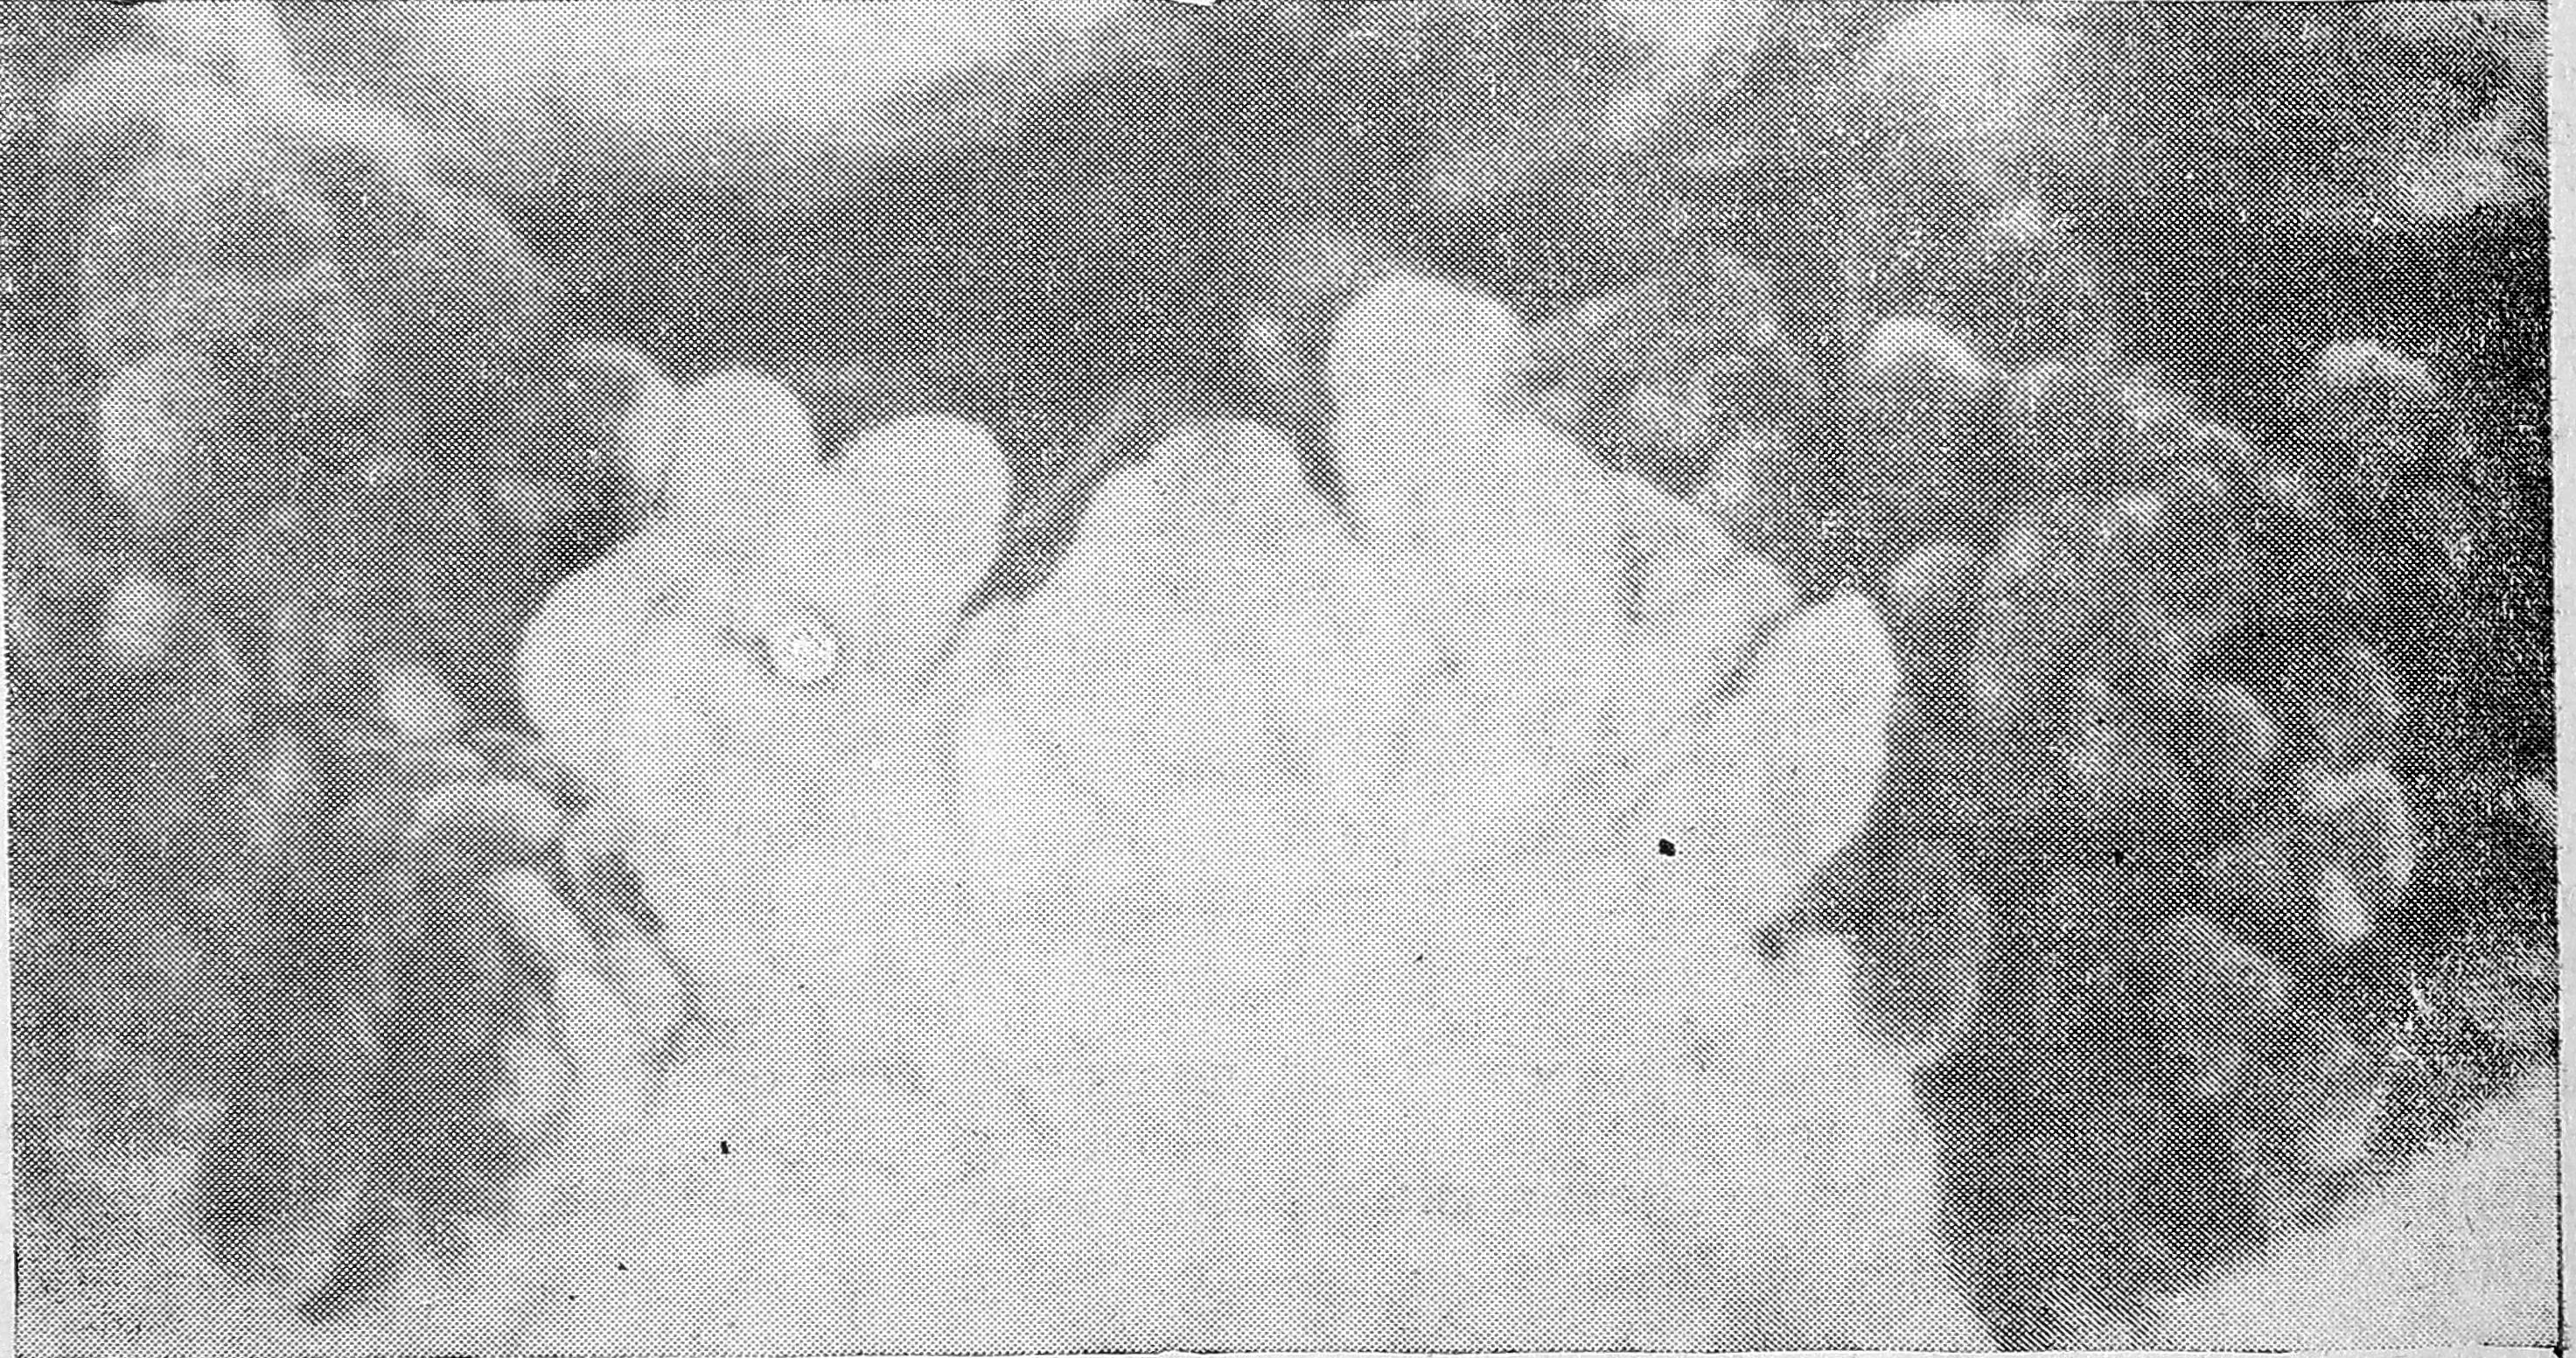

Однако уже анатомические эксперименты показали сравнительно низкие потенциальные возможности этих соустий. Так, например, при перевязке отдельных артериальных ветвей и создании обычного давления при инъекции (когда, наливались артерии всех порядков и все капиллярное русло) вводимая масса в зоне лигированного сосуда совершенно отсутствовала (см. рис.). При создании же повышенного давления (когда инъецировались артерии, капилляры и вены всех порядков) эта масса проникала в область выключенных сосудов только в крупные стволы по межартериальным анастомозам. Аналогичные данные были получены и в экспериментах на венозном русле, где инъекционная масса также только при повышенном давлении обнаруживалась в зоне лигированного сосуда, куда она проникала по межвенозным анастомозам.

Перевязана ветвь селезеночной артерии, идущая к телу поджелудочной железы кошки. Инъекционная масса (при обычном давлении) не проникла в зону лигированного сосуда (ув. 4).